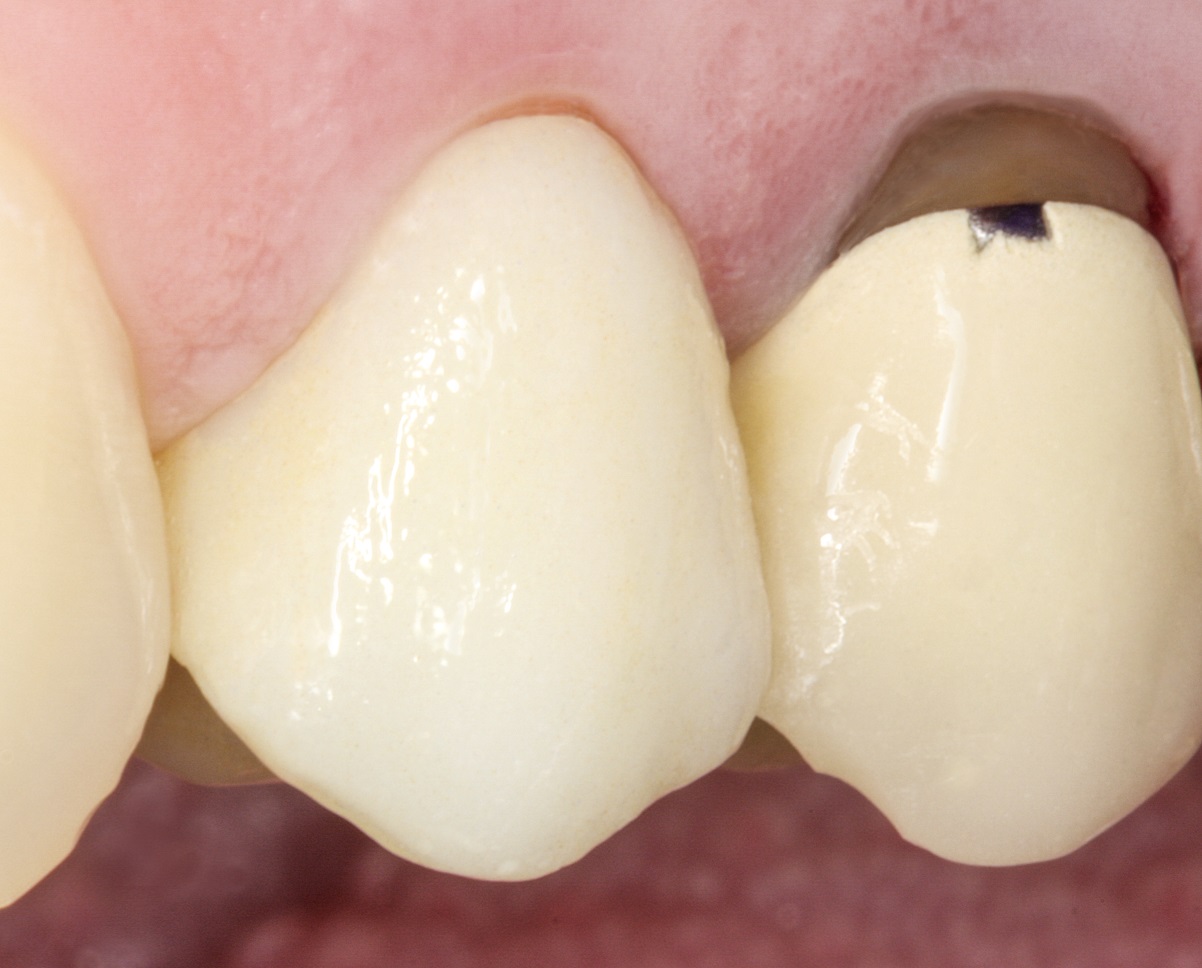

За планом лікування спочатку слід встановити штифт і

сформувати куксу, а потім виготовити коронку на основі дисилікату літію.

Препарування проводиться відповідно до вимог,

встановлених щодо коронок з дисилікату літію (мал. 8).

Фото 8. Зона препарування готова до реставрації.